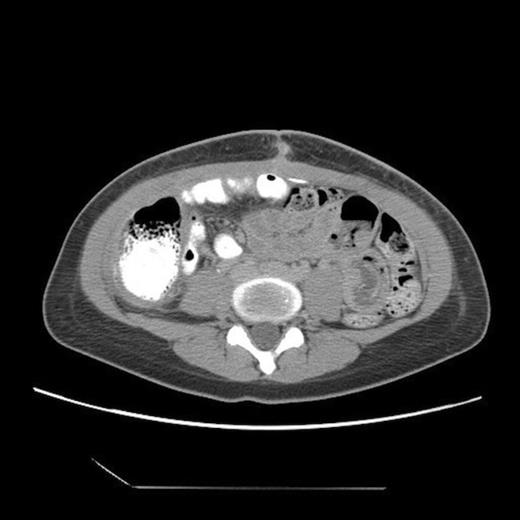

Abdominal CT, axial view, demonstrating a large fluid compartment surrounding the VP shunt catheter resulting in mass-effect, hydronephrosis, and displacement of the intra-abdominal contents

She eventually sought medical attention when she began developing diffuse, unremitting bilateral lower quadrant pain as her abdomen continued to enlarge (Fig. 1). A urine pregnancy test on admission was negative. Abdominal CT demonstrated a large fluid compartment surrounding the VP shunt catheter resulting in mass-effect, hydronephrosis, and displacement of the intra-abdominal contents (Fig. 2 and 3), establishing a diagnosis of APC.